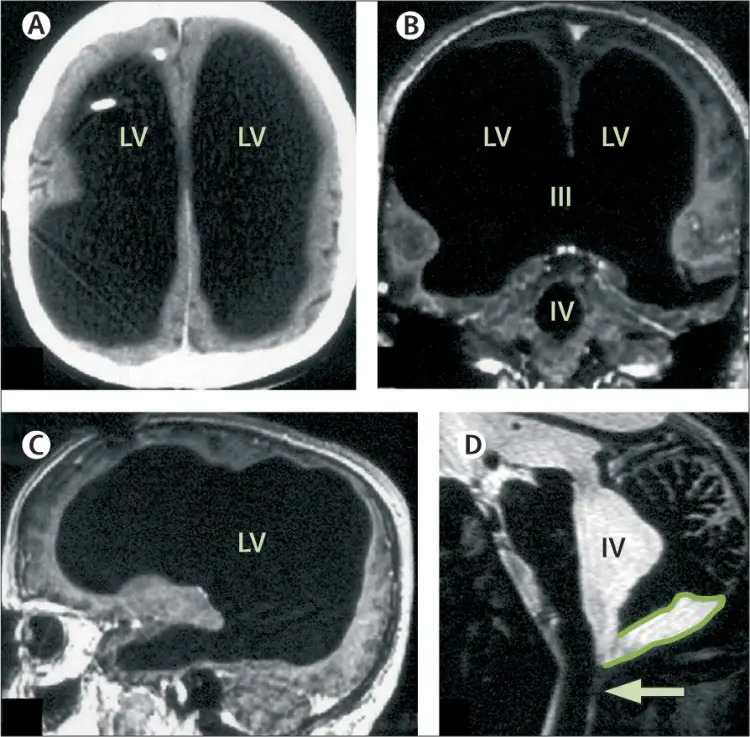

Những hình ảnh chụp CT và MRI từ Bệnh viện Marseille đã ghi lại một thực tế khó tin: phần lớn diện tích mô não được thay thế bằng chất lỏng dịch não tủy. Khi quan sát kỹ hơn qua hình ảnh MRI, thấy rõ rằng lớp mô còn lại cực kỳ mỏng manh chỉ bao phủ quanh thành hộp sọ mà thôi. Điều này càng làm nổi bật sự khác biệt to lớn so với cấu trúc bình thường của một bộ não khỏe mạnh.

Kết quả chụp CT và MRI tại Bệnh viện Marseille

Các xét nghiệm hình ảnh tại bệnh viện cho thấy phần lớn khối lượng mô não đã bị teo nhỏ nghiêm trọng. Quá trình chụp cho phép các chuyên gia xác định chính xác khu vực tổn thương cũng như mức độ thay thế bởi chất lỏng dịch não tủy nằm trong các khoang chứa không gian rộng lớn hơn rất nhiều so với bình thường.

Những khu vực não bị teo nhỏ và thay thế bởi dịch não tủy

Não bộ teo lại chỉ còn lớp mỏng bao quanh hộp sọ

Qua hình ảnh chi tiết, những vùng như vỏ đại não – nơi tập trung cao nhất các chức năng nhận thức – gần như bị tiêu biến hoàn toàn, để lại khoảng trống lớn chứa đầy dịch. Các cấu trúc trung tâm khác cũng bị ảnh hưởng nhưng ít nghiêm trọng hơn nhờ cơ chế thích nghi lâu dài.